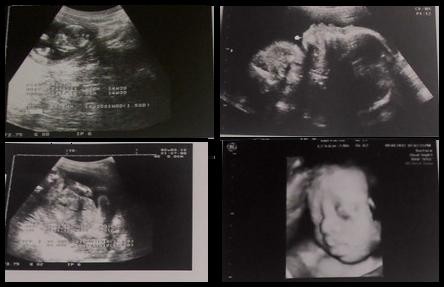

▼奕璇的兒子可能是一個唐氏症寶寶,目前檢查報告尚未出爐。(圖/三采文化提供)

註:目前孩子的檢查報告尚未出爐,希望三采的書友和新聞雲的雲友們,也可以一起替奕璇的兒子集氣加油!